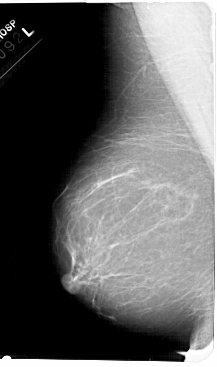

A_1680_1.RIGHT_MLO

A_1680_1.RIGHT_CC

RIGHT_CC LINES 5371 PIXELS_PER_LINE 3106 BITS_PER_PIXEL 12 RESOLUTION 43.5 OVERLAY

RIGHT_MLO LINES 5491 PIXELS_PER_LINE 3091 BITS_PER_PIXEL 12 RESOLUTION 43.5 OVERLAY

FILE: A_1680_1.RIGHT_MLO.OVERLAY

TOTAL_ABNORMALITIES 1

ABNORMALITY 1

LESION_TYPE MASS SHAPE ROUND MARGINS CIRCUMSCRIBED

ASSESSMENT 3

SUBTLETY 3

PATHOLOGY BENIGN

FILE: A_1680_1.RIGHT_CC.OVERLAY